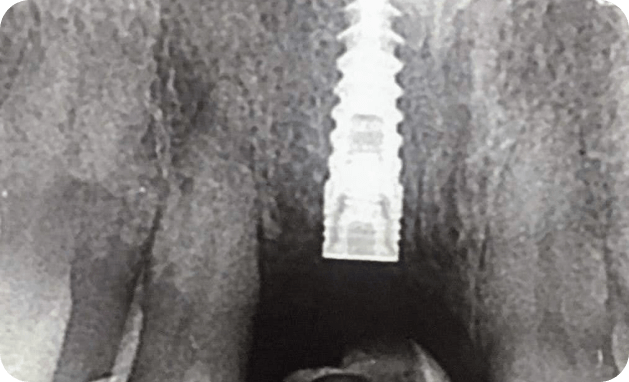

Implantes

Son tornillos en titanio que reemplazan las raices de los dientes.

Implantes de uso en la clínica

MISS, ADIN , ALPHABIO.

Casos